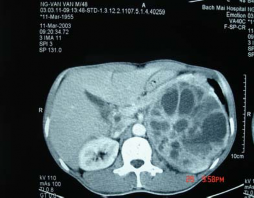

Hình 3.12: U không chế tiết có

đè đẩy; Bệnh nhân số 31

Hình 3.13: Nang tuyến thượng thận; Bệnh nhân số 19